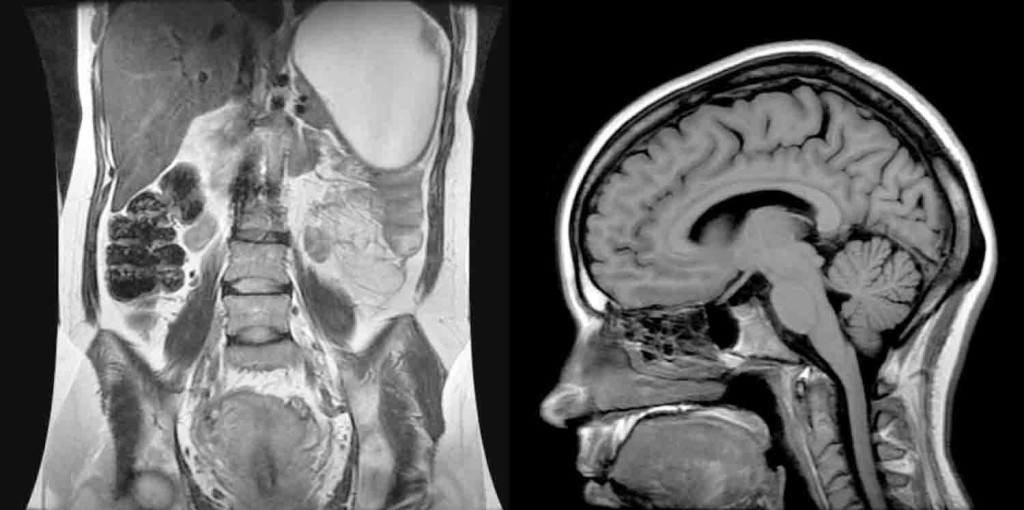

El Centro de Imágenes de La Clínica de la Escuela de Medicina del Recinto de Ciencias Médicas (RCM) cuenta con equipos de resonancia magnética (MRI) y tomografía computarizada (CT Scan) únicos en la región del Caribe.

La tecnología envuelta en la máquina MRI permite hacer estudios avanzados de neuroimágenes, el corazón, las articulaciones y la columna vertebral, entre otras áreas del cuerpo. “Como el equipo tiene tecnología que es bien sofisticada, las imágenes que se producen son mucho mejores. Y en la radiología, mientras mayor sea la resolución de la imagen, mayor es tu capacidad de hacer un diagnóstico que sea preciso”, explicó el doctor Edgar Colón, Decano de la Escuela de Medicina.